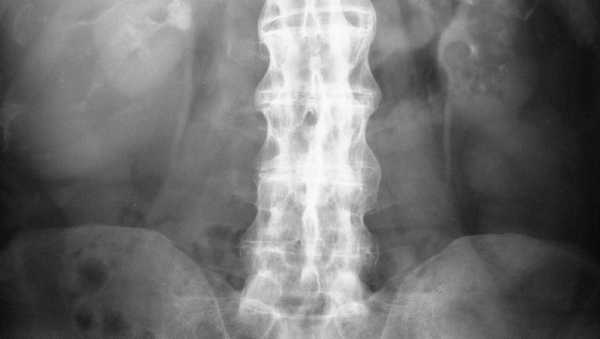

Сросшиеся позвонки на ренгтене.

Основанием для выставления диагноза становятся данные внешнего осмотра пациентки, ее жалобы, результаты инструментальных и биохимических исследований. Женщина также направляется к ортопеду и неврологу для консультации. На полученных рентгенографических изображения отчетливо просматриваются характерные признаки дегенеративно-деструктивной патологии:

- эрозии субхондральной (подхрящевой) кости;

- склеротические изменения, частичный анкилоз;

- сращения крестцово-подвздошных сочленений.

Распространение болей происходит от тазобедренного сустава до шейного отдела позвоночника. После чего у пациента появляется сутулость (позвоночник изгибается в грудном отделе). В таких случаях человек может жаловаться на постоянную напряженность мышц. В дальнейшем патология приводит к полному сращиванию позвонков, окостенению межпозвоночных дисков и формирования костных структур между позвонками. Все это можно детально просмотреть на рентгеновских снимках и результатах МРТ.

Главный анализ, который показан для выявления болезни Бехтерева, — это рентген. На снимке будет явно видна нечеткость суставной поверхности, а также очаг склерозирования. Также специалист определит нарушение вентиляции легких, значительное уменьшение их объема от нормы, которое появляется на фоне нарушения подвижности грудной клетки. В дополнение к этому исследованию пациентке назначают пройти МРТ, чтобы выяснить, не имеются ли органические поражения в позвоночнике, и тогда диагноз будет совершенно другим.

У молодых женщин болезнь начинается с поражения периферических суставов, затем патологический процесс переходит на тазобедренные суставы (коксартроз). Позвоночный столб, как правило, редко поражается полностью. На рентгеновских снимках «симптом бамбуковой палки» имеет ограниченную протяженность.

Данный симптом характеризуется искажением тел позвонков, которые приобретают квадратную форму. Замыкательные пластинки, отделяющие межпозвоночные диски от тел позвонков, уплотняются. В результате позвоночник или его часть становятся похожими на бамбук, что хорошо видно на рентгене.

Основным инструментальным диагностическим методом является рентгенография, выполняемая в прямой и боковой проекции. На снимках можно увидеть двустороннее воспаление крестцово-подвздошного сочленения, наличие остеопороза в телах позвонков, уменьшение высоты дисков и признаки артроза фасеточных суставов. Рентген тазобедренного сустава показывает сужение межсуставной щели, в запущенных случаях головка бедренной кости оказывается вдавленной в суставную впадину.